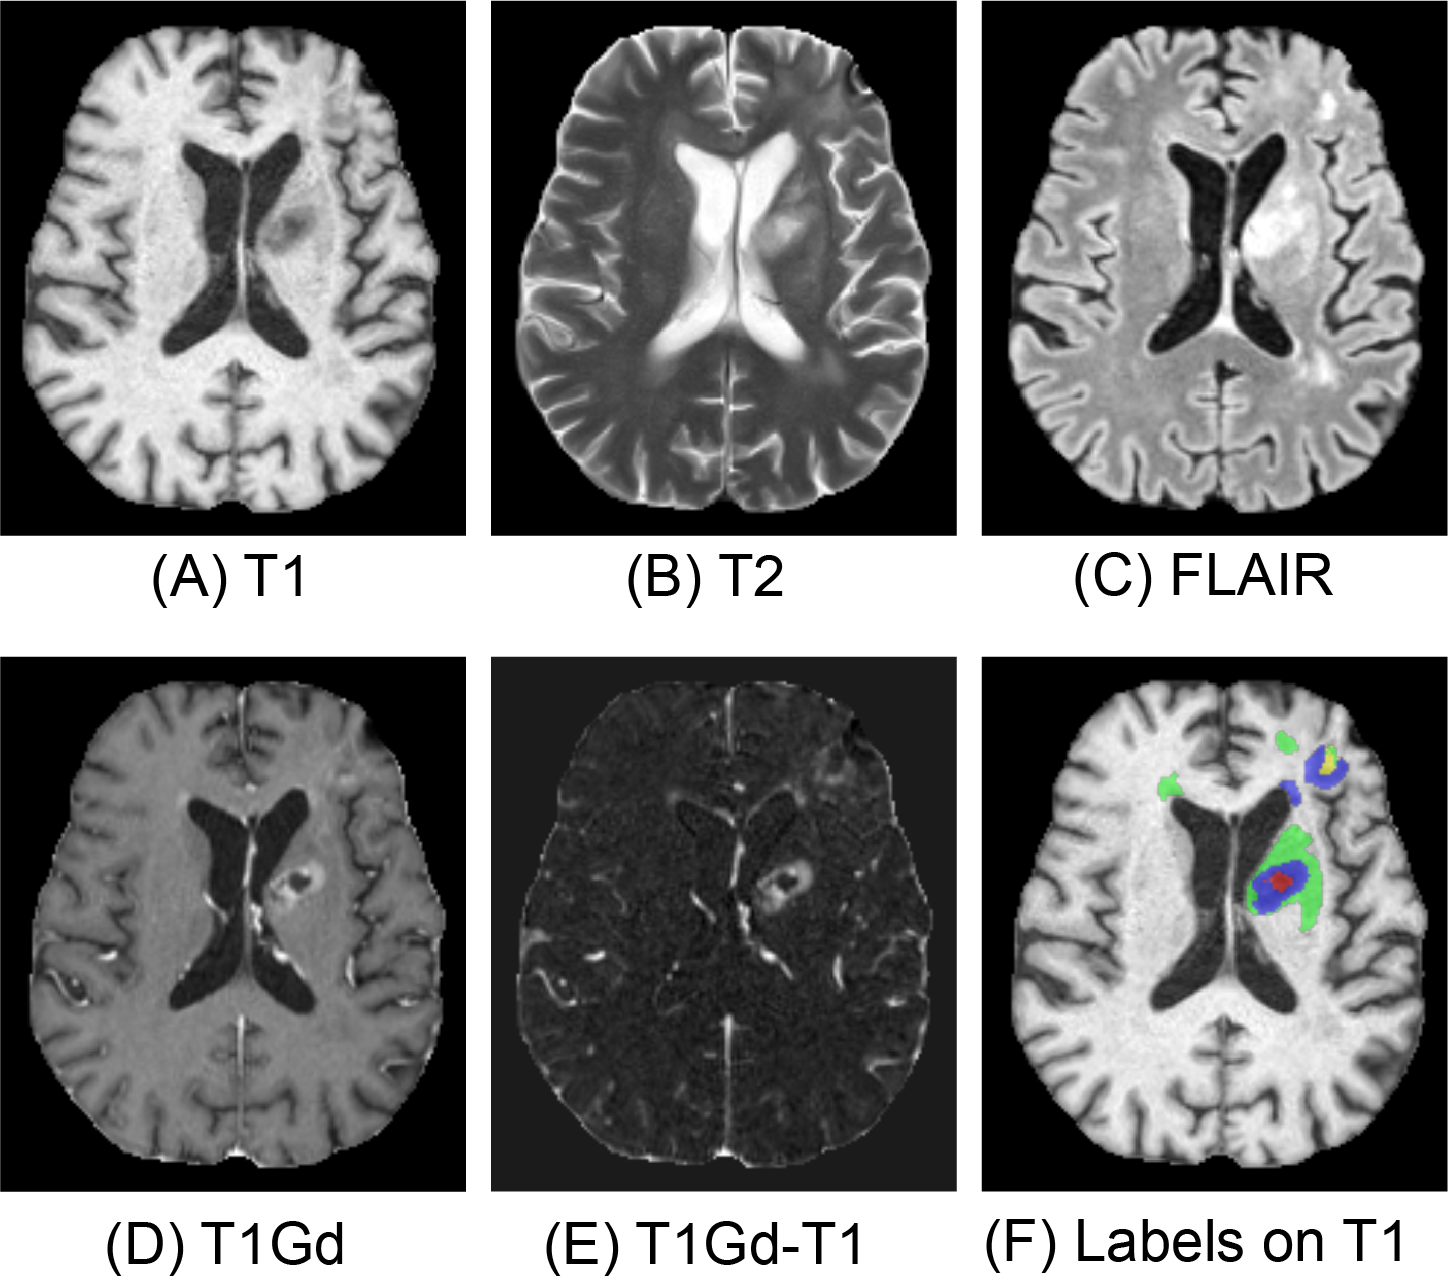

During the curation of the 2024 challenge dataset, annotators were provided with the T1 contrast subtraction (T1Gd-T1) image for segmentation [24]. Inspired by this, we used the T1Gd - T1 image as an additional input. In Figure 1, T1Gd-T1 highlights the ET.

Figure 1: Four MR imaging modalities from the 2024 BraTS challenge dataset (A-D) and a calculated modality (T1Gd-T1, E). Tumor sub-region labels (F) include enhancing tissue (ET, blue), non-enhancing tumor core (NETC, red), surrounding non-enhancing FLAIR hyperintensity (SNFH, green), and resection cavity (RC, yellow).